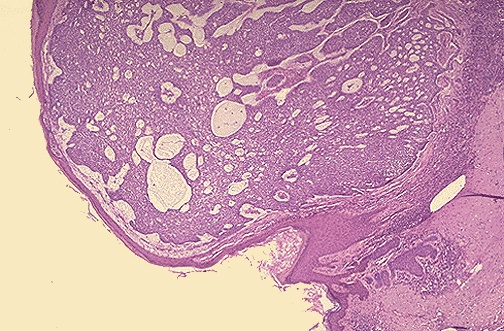

| This is a basal cell carcinoma (BCC). A BCC is probably the most common skin malignancy. A BCC can grow quite large and invade surrounding tissues, but it virtually never metastasizes. The BCC above is growing as a nodular mass. BCC's around the eye present a challenge to the surgeon to remove and retain functionality of the eyelid. Therefore: detect BCC's early and treat them when they are small! |